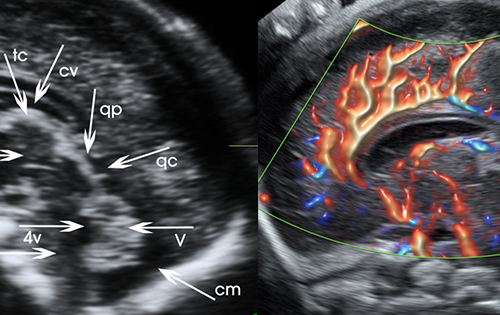

Advanced ultrasound, screening, and diagnostic services for accurate fetal and maternal health assessment.